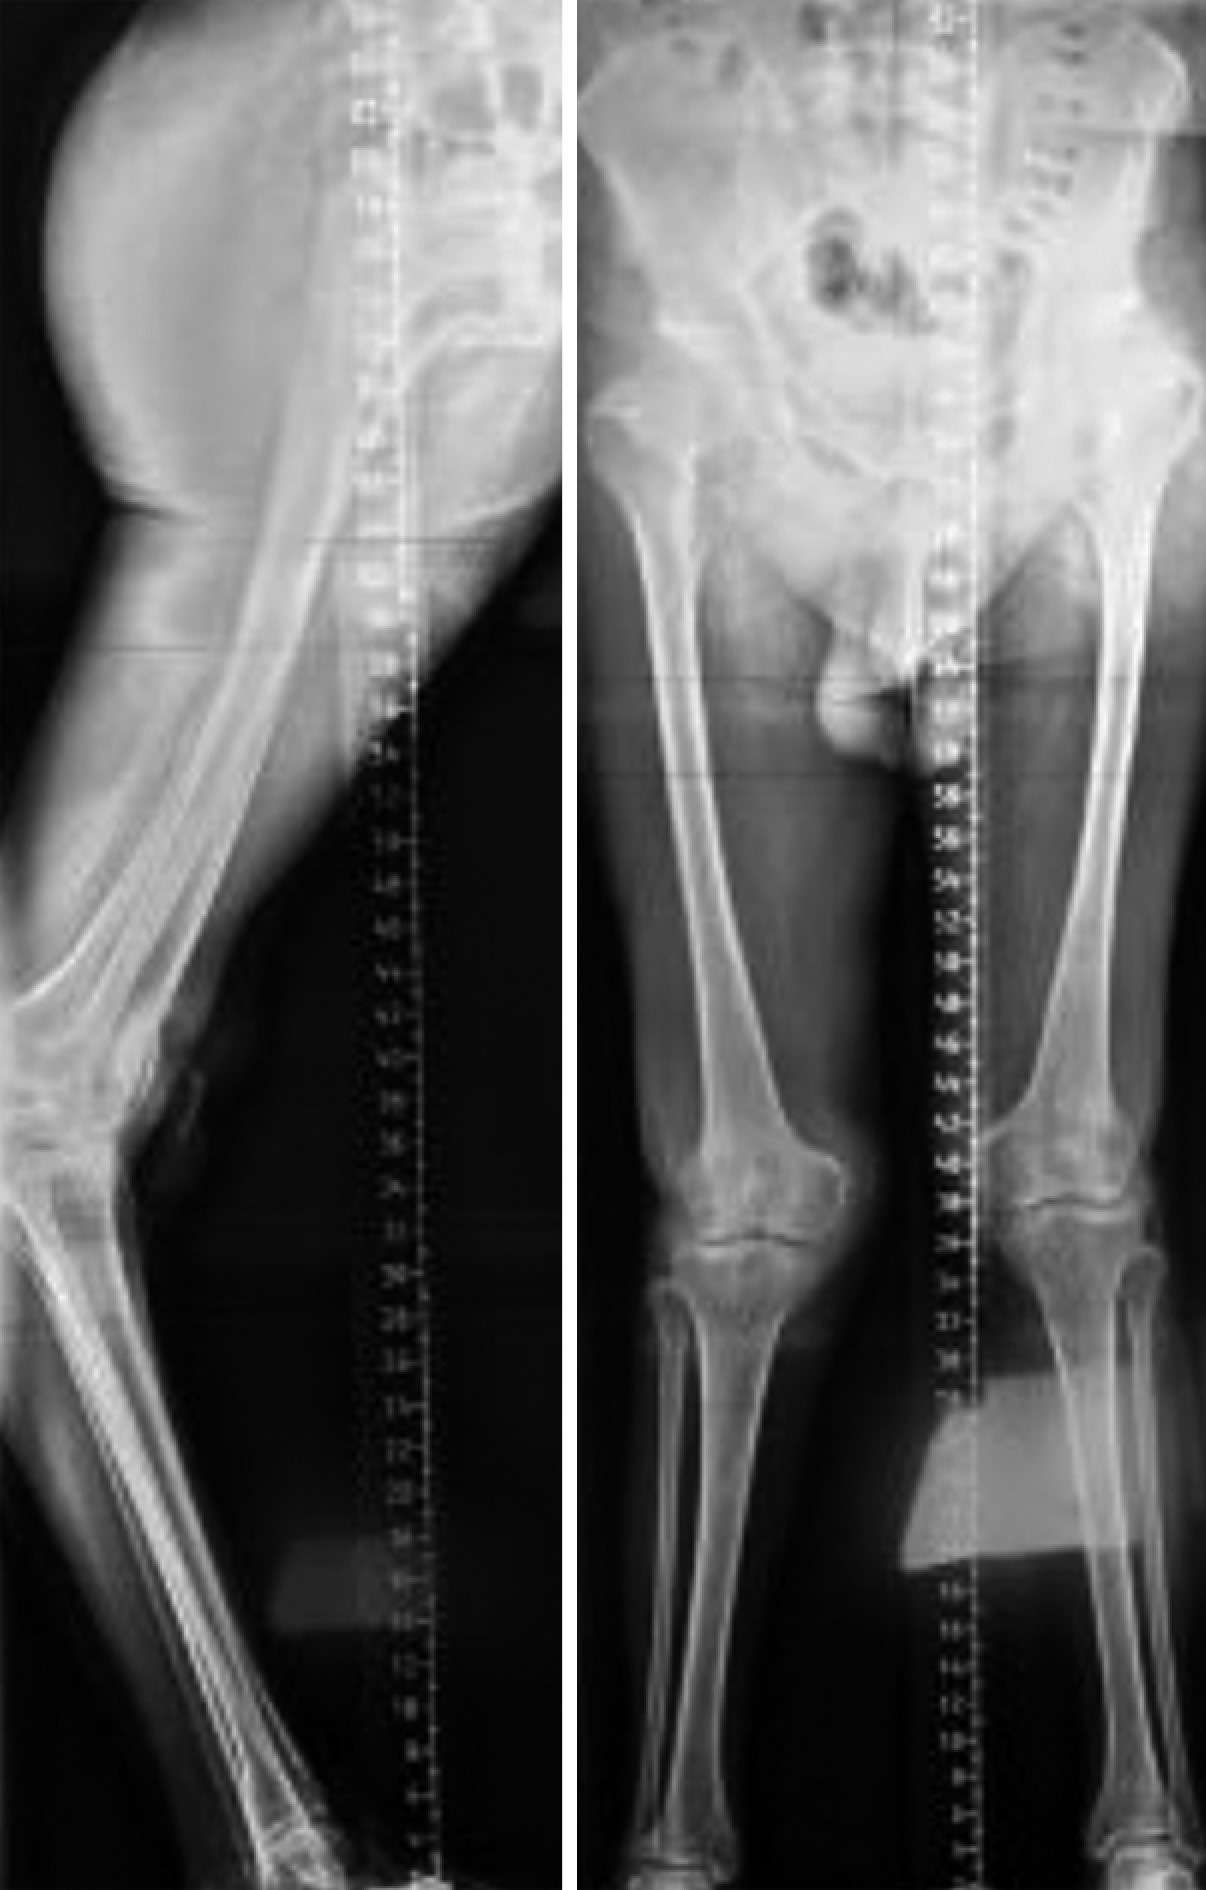

При поступлении. В сентябре 2019 г. пациент был госпитализирован для проведения первым этапом оперативного вмешательства на правом коленном суставе. У пациента отмечалась двусторонняя фиксированная вальгусная деформация нижних конечностей около 5–7° на уровне коленных суставов с двусторонней гиперэкстензией, увеличивающейся при нагрузке до 40°, таким образом, объем движений в коленных суставах составлял -40...0...110°. При ходьбе он вынужденно блокировал коленные суставы в положении гиперэкстензии, что типично для пациентов с парезом нижних конечностей после перенесенного полиомиелита (рис. 1).

Рис. 1. Внешний вид пациента до операции

Figure 1. The patient’s appearance before surgery

Пассивное сгибание в коленных суставах ограничено не было и достигало 130°, активное сгибание — 110°. Сила четырехглавых мышц бедра с обеих сторон оценивалась в 2 балла из 5 по общепринятой клиническими неврологами системе Medical Research Council Scale (MRC) [3], что означает возможность полного объема движений только после устранения силы тяжести (конечность помещается на опору). В правом голеностопном суставе — полное отсутствие активных и пассивных движений, в левом — объем пассивных движений в пределах 5°, активные движения отсутствовали. Рентгенологически у пациента отмечался двусторонний гонартроз 3 ст., вальгусная деформация нижних конечностей на уровне коленных суставов (справа и слева около 10°), ограниченные дефекты латеральных мыщелков обеих большеберцовых костей, диспластические изменения мыщелков бедренных и большеберцовых костей, надколенника (рис. 2). Итоговый показатель по адаптированной шкале Knee Society Score (KSS) [4] составлял 25 баллов.

Рис. 2. Полноразмерные снимки нижних конечностей с нагрузкой до операции

Figure 2. Full-length X-rays of the lower extremeties under load before surgery